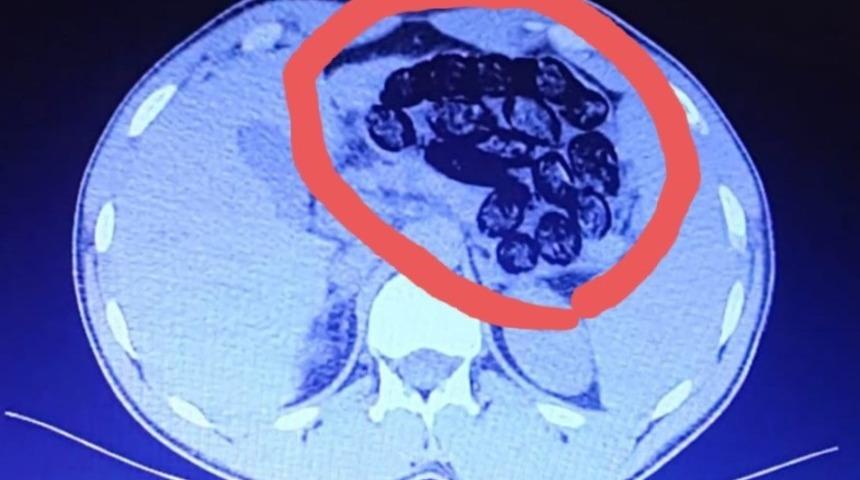

Van'da havalimanına giden 2 İranlı'nın mide filminde 103 adet kapsül halinde 920 gram metanfetamin maddesi olduğu saptandı. İzmir'e gitmek isterken yakalanan kişiler tutuklandı.

Açıklamada, “Şahısların Van-İzmir uçağına binişleri engellenmiş, alınan karara istinaden yapılan iç beden muayenesinde şahısların midelerinde kapsül halinde yabancı cisimler olduğu görülmüş. Yapılan iç beden muayenelerinden sonra taburcu edilmişler ve şahıslarda A.D.’den 52 adet kapsül halinde 460 gram, S.A.’dan ise 51 adet kapsül halinde 460 gram olmak üzere toplamda 103 adet kapsül halinde 920 gram metanfetamin maddesi ele geçirilmiştir. Elde edilen uyuşturucu maddeyle ilgili olarak gözaltına alınan A.D. ve S.A. isimli şahıslar, sevk edildikleri adli makamlarca tutuklanmışlardır” denildi.